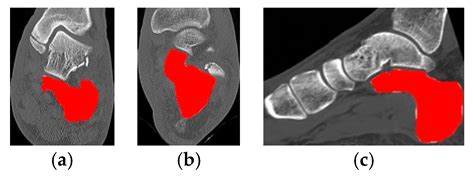

Calcaneal Fracture Types

Real-Time Automated Segmentation and Classification of Calcaneal ...